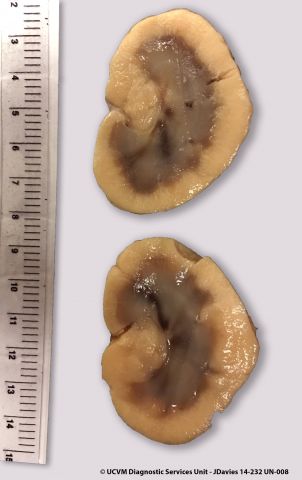

Equid, Horse: Brain, trimmed. Normal trimmed brain.